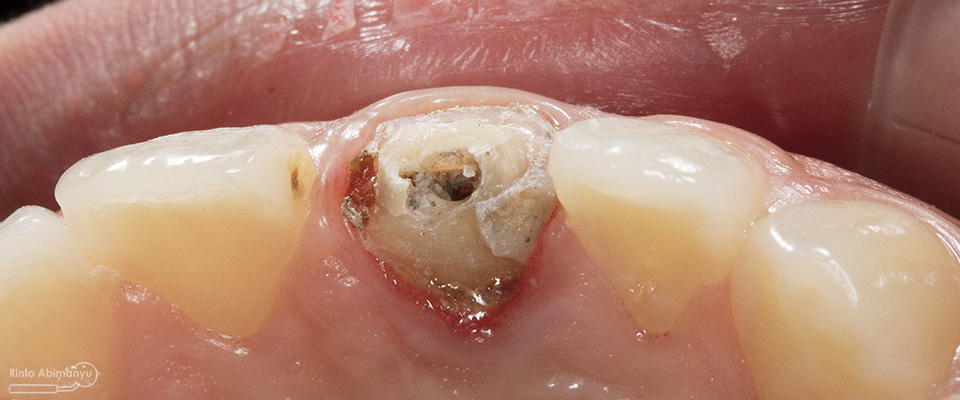

Begini kondisi klinis saat datang…

Foto klinis gigi-gigi anterior yang mengalami fraktur